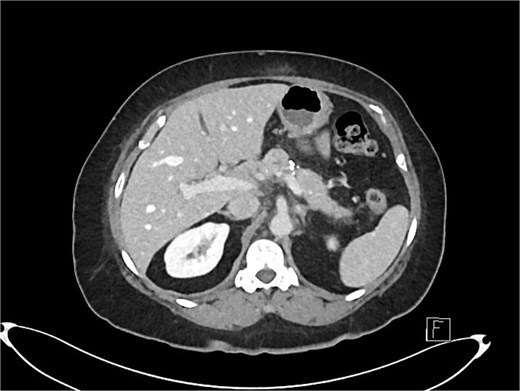

Post-operatively, a CT multiphase liver showed calcifications within the pancreas consistent with chronic pancreatitis, but there was no lymphadenopathy, no evidence of malignancy, and the rest of the abdominal organs were unremarkable in appearance (Fig. 3).

Axial slice of post-operative CT scan showing features of chronic pancreatitis.